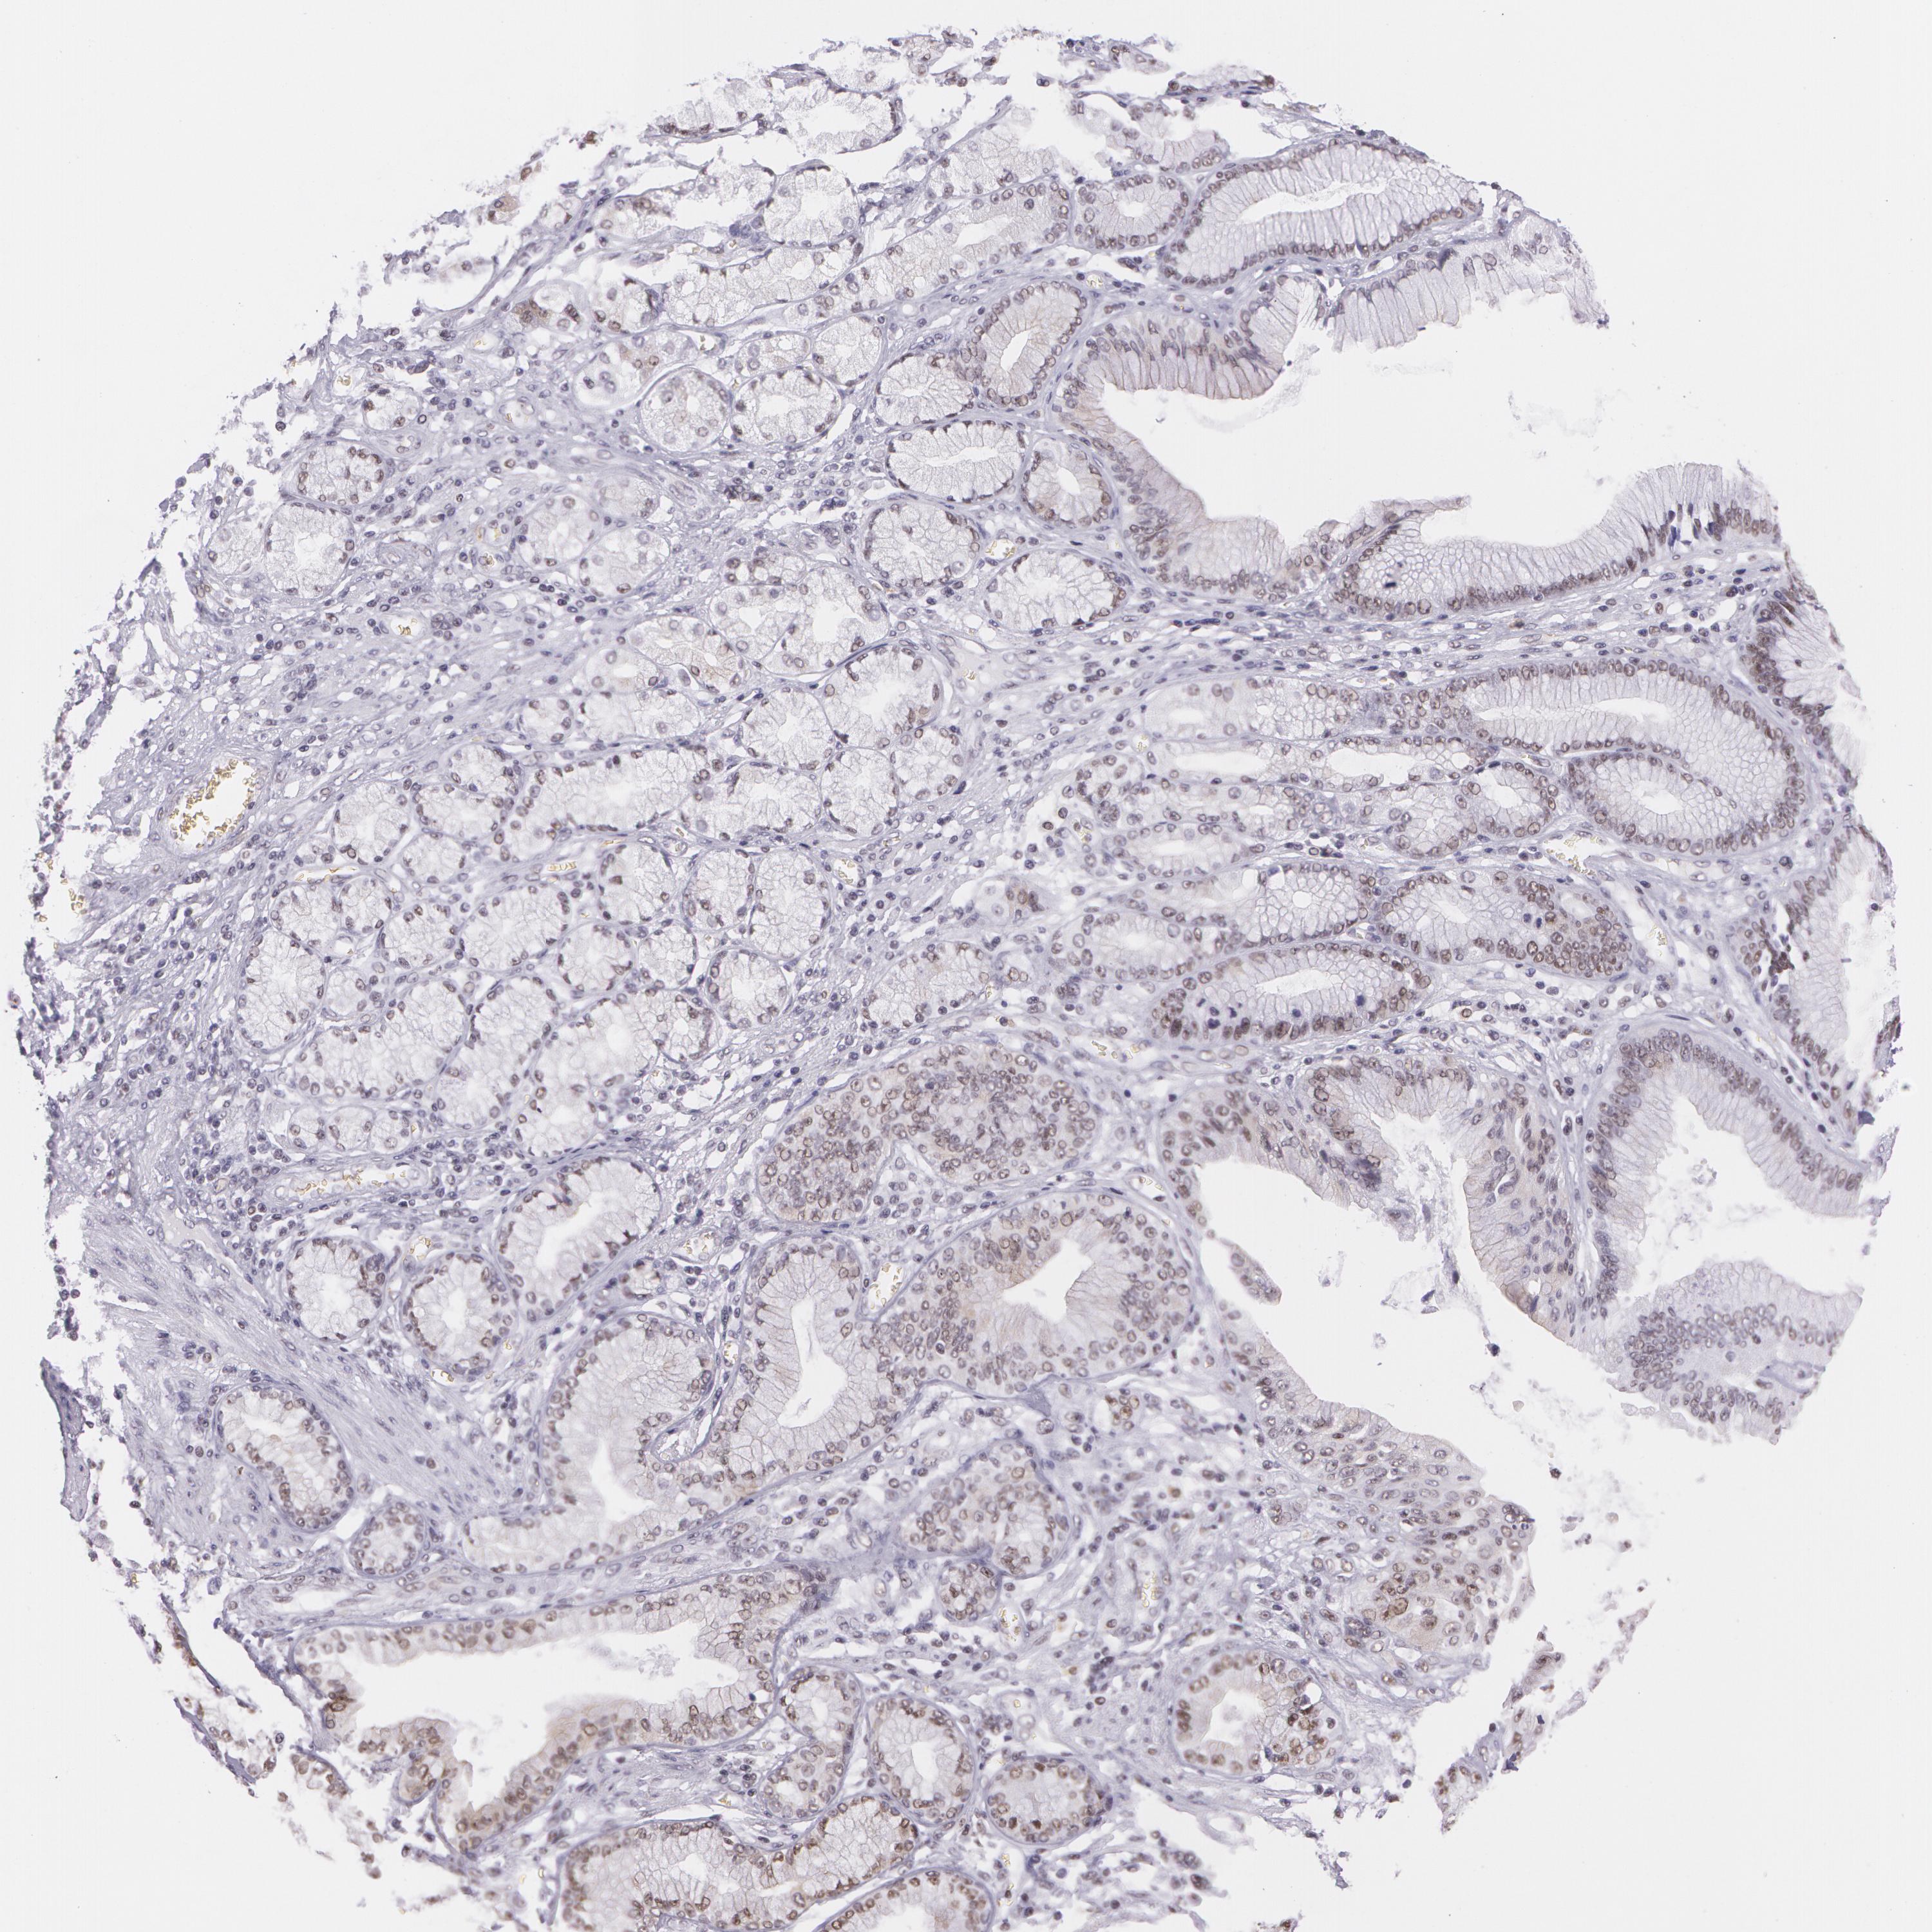

STOMACH CANCER - Protein expressioni

A mouse-over function shows sample information and annotation data. Click on an image to view it in a full screen mode. Samples can be filtered based on level of antibody staining by selecting one or several of the following categories: high, medium, low and not detected. The assay and annotation is described here.

Note that samples used for immunohistochemistry by the Human Protein Atlas do not correspond to samples in the TCGA dataset.

Antibody stainingi

Antibody staining in the annotated cell types in the current human tissue is reported as not detected, low, medium, or high, based on conventional immunohistochemistry profiling in selected tissues. This score is based on the combination of the staining intensity and fraction of stained cells.

Each image is clickable and will lead to virtual microscopy that enables deeper exploration of all samples and also displays staining intensity scores, fraction scores and subcellular localization as well as patient and tissue information for each sample.

Antibody HPA001429

Antibody CAB003836

Antibody CAB080233

Staining

High

Medium

Low

Not detected

Intensity

Strong

Moderate

Weak

Negative

Quantity

>75%

75%-25%

<25%

None

Location

Nuclear

Cytoplasmic/membranous

Cytoplasmic/membranous,nuclear

Adenocarcinoma, NOS

Adenocarcinoma, High grade